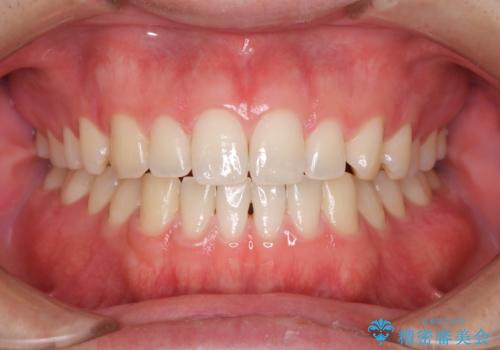

- 虫歯予防のため、クリーニングと歯磨き指導を希望とのことでした。PMTC30分コース、歯磨き指導を行いました。

日々の歯磨きを上達するには、まずどこが磨けていないか認識することが大切です。